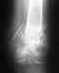

В 2010 году имел место подвывих копчика в результате падения с высоты. После этого отлежался на больничном две недели и забыл об этом инциденте. В результате неудачного падения (подскользнулся) в начале 2013 года появилась боль в промежности, отдающая в гениталии (только при сидении и в результате сидения - сильные тянущие ощущения, некоторое онемение, покалывание, дискомфорт) Поставили диагноз (уролог) - простатит. Прошёл полный курс лечения от него (бактериальная флора, к слову, так и не была обнаружена ни в одном из анализов, поэтому и лечился от абактериального). Результат - ноль. Врач сказал, что дело, возможно, в неврологии (остеохондроз). Сделал МРТ пояснично-крестцового отдела позвоночника: "Лёгкая протрузия 3 мм L5-S1". В ГКБ 40 (нейрохирургия) врач сказал, внимательно рассмотрев снимки МРТ, что такая протрузия, тем более на таком участке позвоночника, никак не может давать такие сильные тянущие боли в паху, и что виноват тот самый подвывих копчика в 2010 и "освежившая" его недавняя травма. Что, возможно, так как он загнут на 90 градусов вовнутрь (что видно по снимку рентгена), пережимает какие-то нервы и/или сосуды. Что может даже понадобиться удаление копчика, если болевую симптоматику ничем не удастся снять.Занимаются ли у вас лечением кокцигодинии (она ли это, если сам копчик не болит, болят только гениталии после сидения) и проводятся ли операции по удалению копчика, если таковая будет показана?Спасибо!